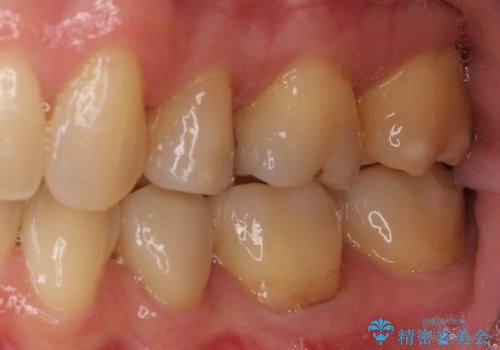

矯正の後戻りの改善と銀歯をセラミックに

- 上下前歯の叢生を気にして来院された患者様です。

費用を抑え、期間もあまりかけずに治療をしたいとのことで、インビザライン・ライトを用いて矯正治療を行うこととしました。

矯正治療後には、下顎臼歯の目立つ銀歯をセラミックインレーにて修復治療を行いました。

口を開けたときに金属が見えなくなり、患者様には大変満足していただきました。